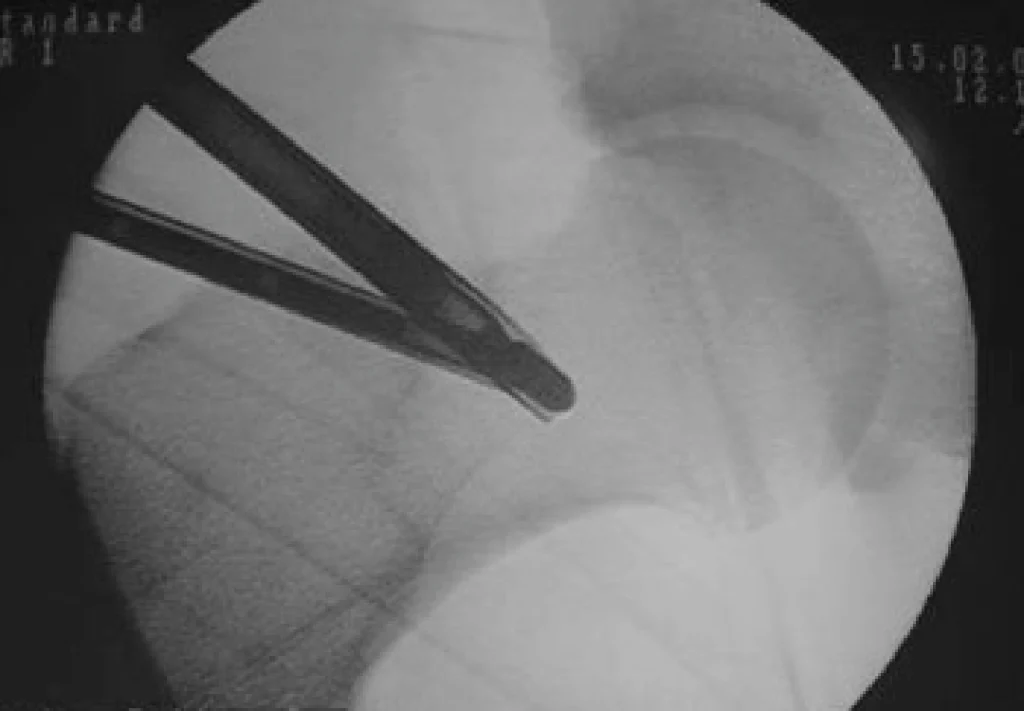

Há pelo menos 30 anos, a videoartroscopia tem se estabelecido como uma poderosa arma no arsenal do cirurgião ortopedista. A artroscopia é uma técnica para cirurgia minimamente invasiva. Através dela, o cirurgião não precisa ver a articulação diretamente com seus olhos. Ele utiliza pequenos orifícios na pele, por onde insere um dispositivo de fibra óptica (artroscópio) conectado a um equipamento de vídeo de alta resolução, através do qual o cirurgião pode acessar as diferentes partes da articulação e inserir instrumentos para manipular e tratar os tecidos lesados.